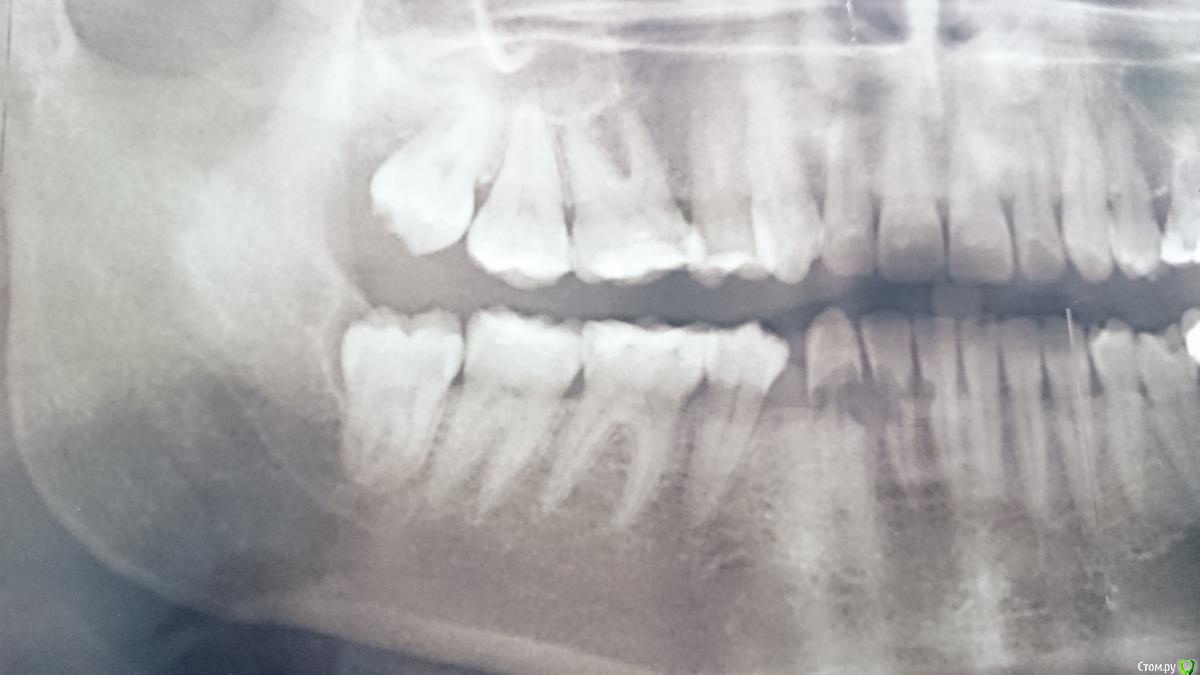

vse32 Опубликовано 16 марта, 2018 Поделиться Опубликовано 16 марта, 2018 Пару снимков за этот месяц. Прямо закон парных случаев.Оба 46. Внутренняя перфарирующая резорбция. Оба трупы. В обоих случаях точная причина не известна.Возможно спровацированно лечением глубокого кариеса. 6 Ссылка на комментарий